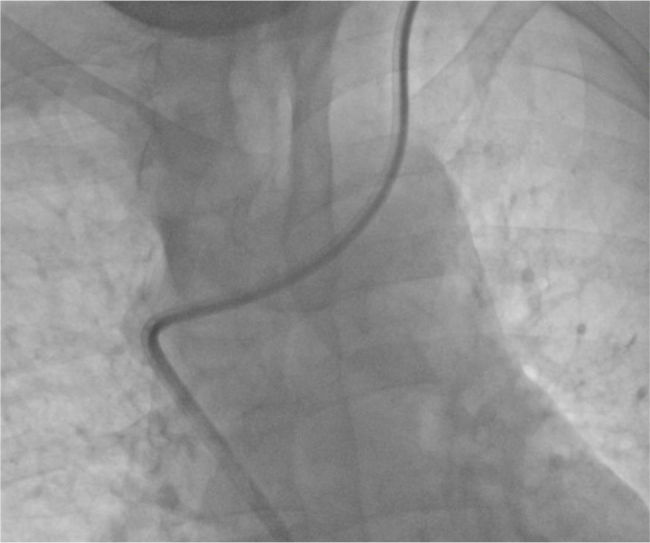

Case description: We report on a 68-year-old male on haemodialysis with SVC perforation and stenosis due to prolonged catheter use. After a failed guidewire-assisted exchange, a non-tunnelled CVC was successfully placed in the enlarged azygos vein under fluoroscopy. The patient continued haemodialysis without complications, and the two-month follow-up confirmed catheter patency.